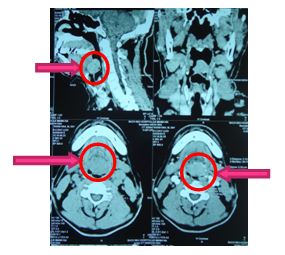

+ Kết quả chụp cắt lớp vi tính 64 dãy vùng hầu họng:

Hình 8. Hình ảnh chụp cắp lớp vi tính vùng cổ sau điều trị xạ trị + Hoá trị 6 đợt:

Nốt sùi đáy lưỡi kích thước 12x10 mm, ngấm thuốc mạnh không đều sau tiêm, một phần dính vào nắp thanh môn bên trái.

+ Kết quả nội soi tai mũi họng: Không thấy khối u vùng đáy lưỡi